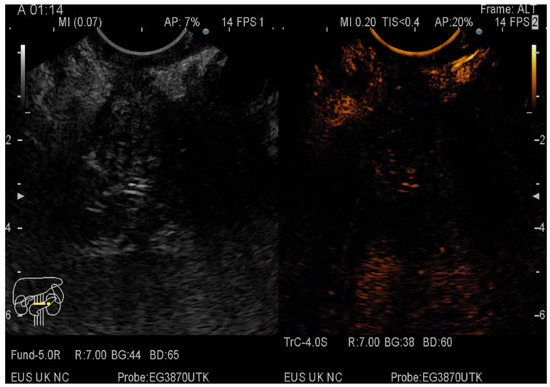

2.5. CE-EUS Procedure

3.3. EUS-FNA/FNB + CE-EUS of Pancreatic Cystic Lesions Subgroup